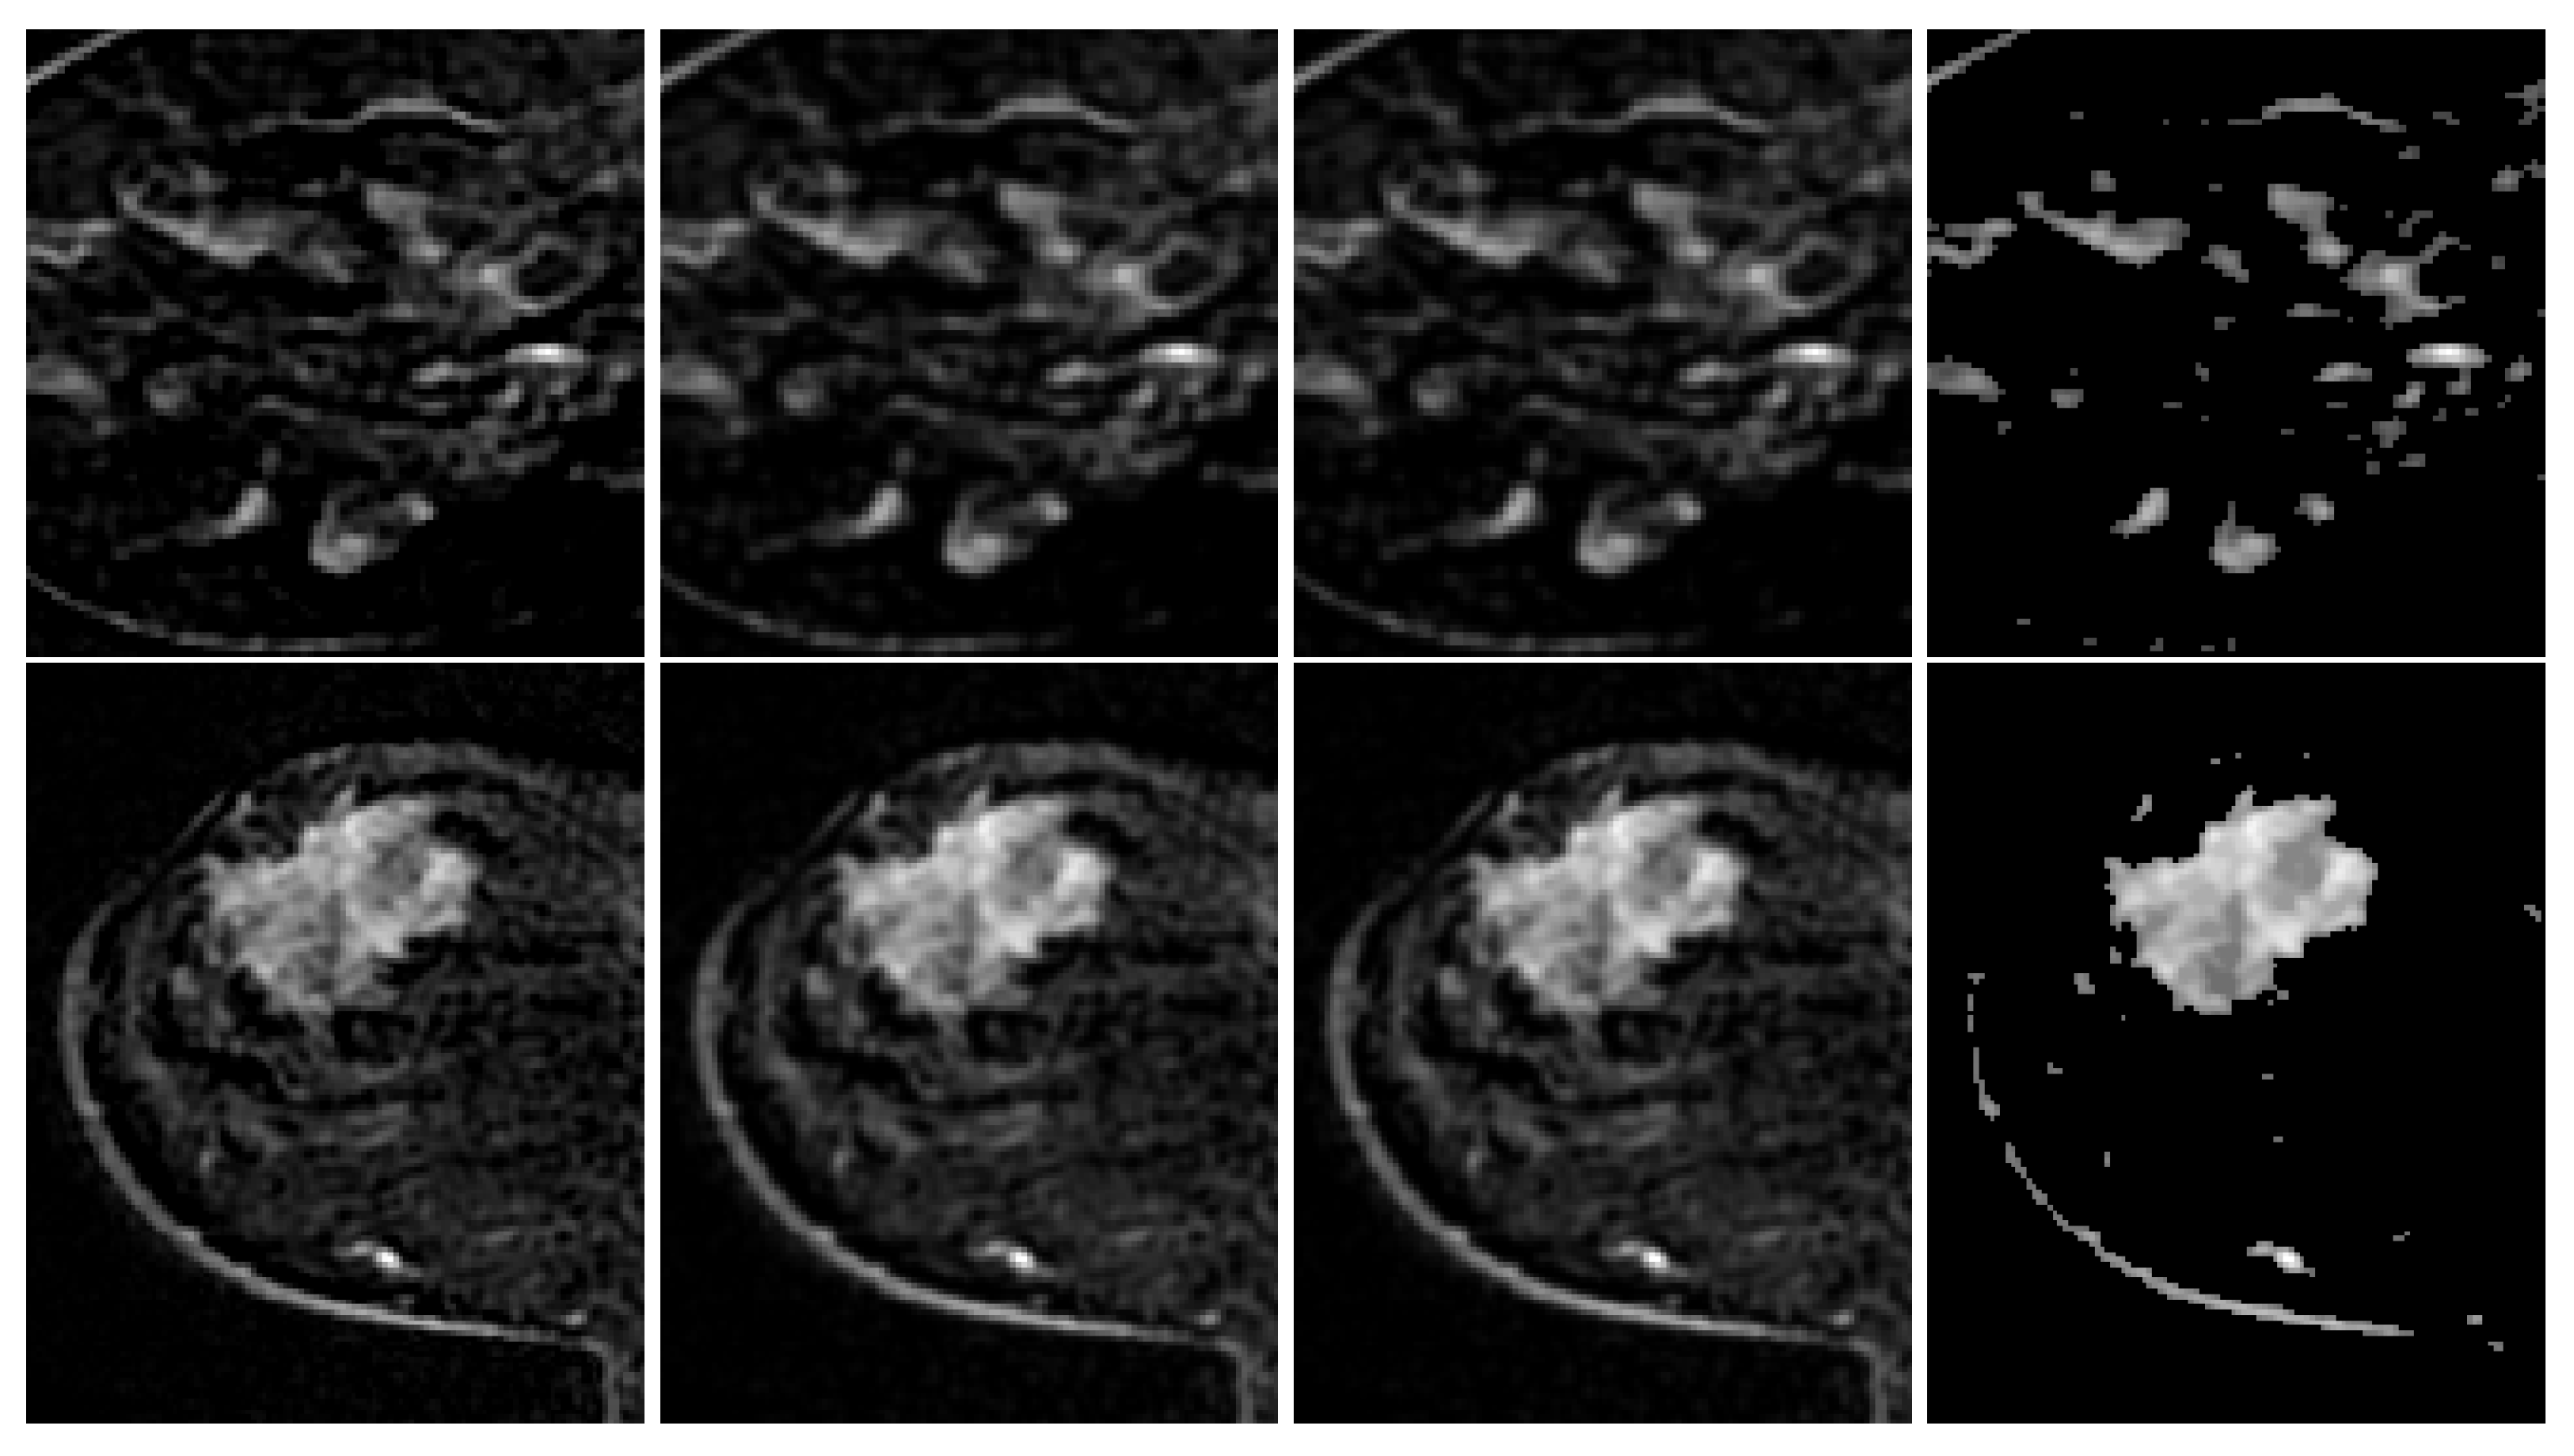

3.2.2. Pre-Processing

3.2.3. Segmentation

3.2.4. Post-Processing